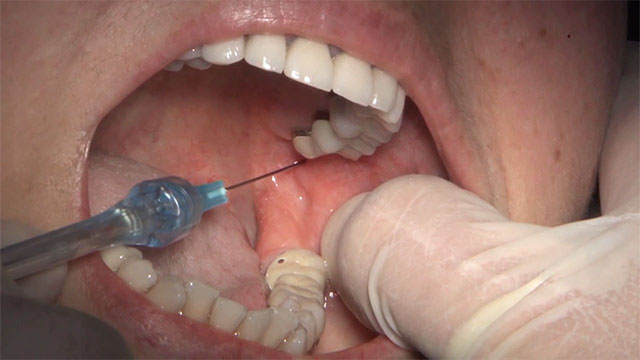

Bước 2: Gây tê tại vị trí nhổ răng khôn hàm dưới

Trước khi gây tê, khoang miệng của bệnh nhân cần được vệ sinh răng miệng sạch sẽ. Thuốc tê giúp bệnh nhân giảm bớt đau đớn, khó chịu và quá trình nhổ răng diễn ra thuận tiện hơn.